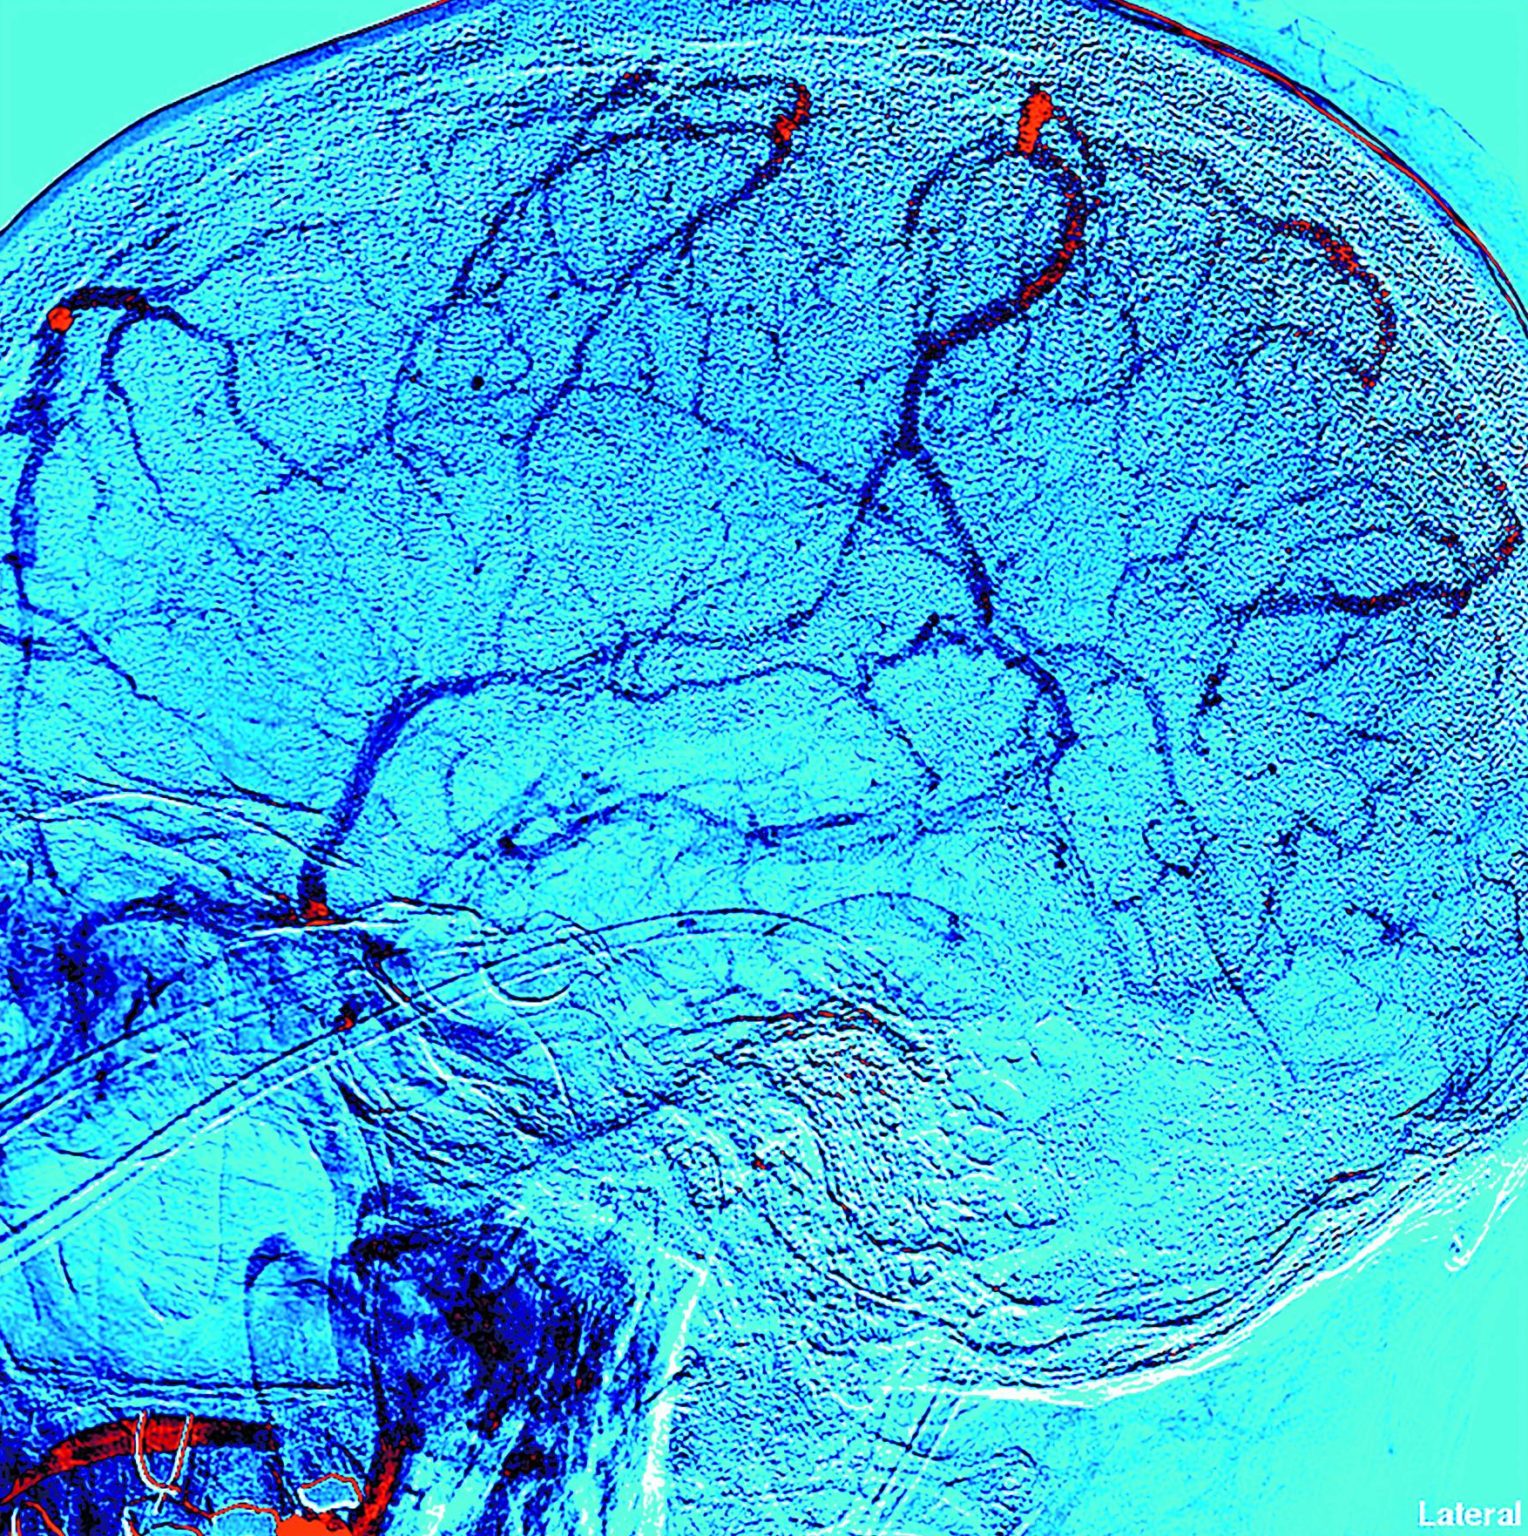

Le diagnostic peut se faire lors de la surveillance échographique de la grossesse, le plus souvent au deuxième ou troisième trimestre de grossesse, notamment lorsqu'il existe un hydramnios ou d'autres malformations associées. L'utilisation d'échographie 3D ouvrirait la possibilité d'une détection plus précoce, au premier ou deuxième trimestre,.